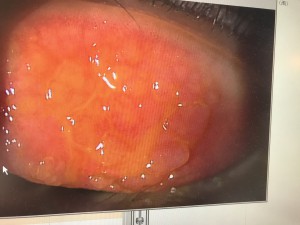

9月初め頃から、例年、花粉症で悩まされている方には、抗アレルギー剤の目薬や内服薬を処方しております。その中で、特に、目の症状がかゆいを通り越して、痛くて目が開けられないと訴えてこられる患者さんがおられます。よくみると、上のまぶたの裏の結膜に巨大乳頭結膜炎をきたし、角膜に潰瘍などを生じています。潰瘍に、細菌感染を来すと、角膜が混濁し、治っても、視力障碍が残ることがあります。原因は、体質的な関連のこともありますが、コンタクトレンズ使用されている方だと、その大半は、コンタクトレンズのケアが、行き届いてないため、です。 コンタクトレンズを付けたまま寝たり、2週間用のレンズを使用期間を超えてつかったり、毎日の洗浄をいい加減にしますと、必ず発症しますから、気を付けてください!

写真は、巨大乳頭結膜炎についての写真です。